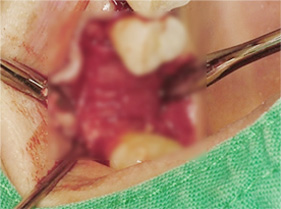

인공뼈 및 가가골 이식 (뼈 이식)

뼈의 재생을 유도 (골유도재생술)